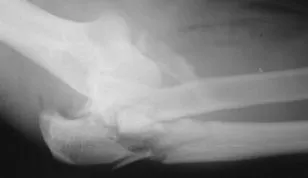

A complete elbow dislocation.

A simple dislocation does not have any major bone injury.

A complex dislocation can have severe bone and ligament injuries.

In the most severe dislocations, the blood vessels and nerves that travel across the elbow may be injured. If this happens, there is a risk of losing the arm.